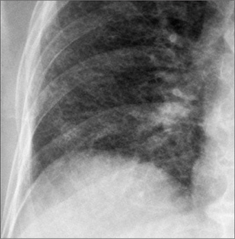

Figure 21.6 Male. Cavitating nodules. Metastatic lesions from a primary tumour of the larynx. Metastases that cavitate are usually squamous cell lesions: in men, frequently a head and neck primary tumour; in women, often carcinoma of the cervix.